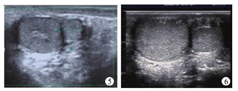

例3 男,4岁,因无意间发现右侧阴囊内肿物1月余就诊于我院门诊。查体见右侧阴囊内睾丸下方可及一类圆形肿物,大小约8 mm×7 mm×5 mm,边界清,质地较硬,活动度可,无触痛、按压痛。彩色超声检查示:双侧睾丸不等大,左侧大小约19 mm×16 mm×15 mm,右侧大小约14 mm×12 mm×11 mm,包膜光滑,回声均匀,右侧睾丸下方可见一大小约8 mm×6 mm×5 mm实性等回声,边界清晰,内回声均匀,与睾丸组织相类似(考虑多睾症)。实验室检查示甲胎蛋白及绒毛膜促性腺激素均在正常参考值范围内。采取保守治疗,定期复查。患儿采取保守治疗,每年复查一次彩色超声检查均提示多睾症(图5、图6),复查甲胎蛋白、绒毛膜促性腺激素均在正常参考值范围,随访5年至今,未见明显不适。